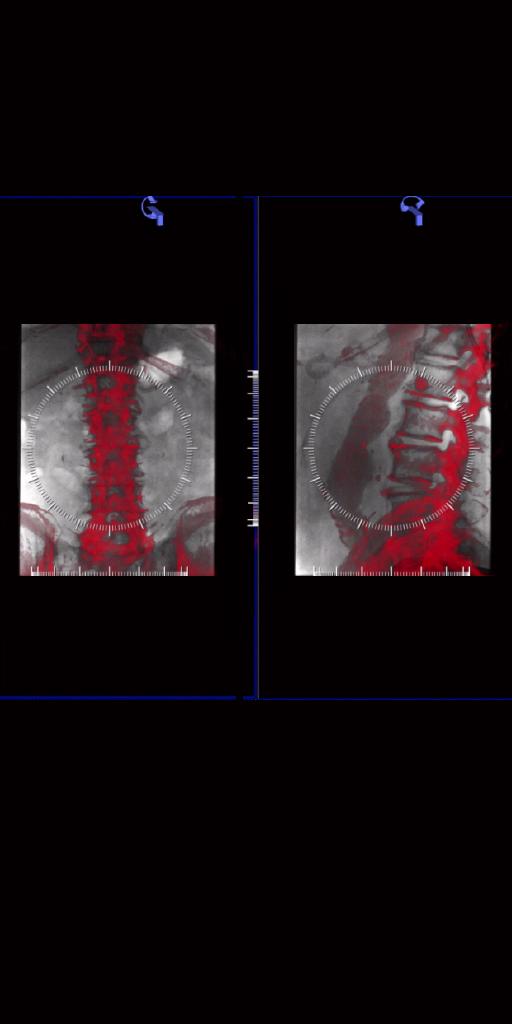

syngo DynaPBV Body

La famille ARTIS icono est dotée de l’application syngo DynaPBV Body, qui complète l’imagerie anatomique par des informations physiologiques. Il est ainsi possible de disposer d'images du volume sanguin en 3D, afin de déterminer les caractéristiques spécifiques de chaque lésion et d’observer l'évolution de la perfusion des tumeurs en fonction du traitement.

Ce logiciel permet de surveiller la réponse au traitement post-TACE

répété et aider à identifier les non-répondants au traitement thérapeutique

sans quitter la salle d’angiographie.